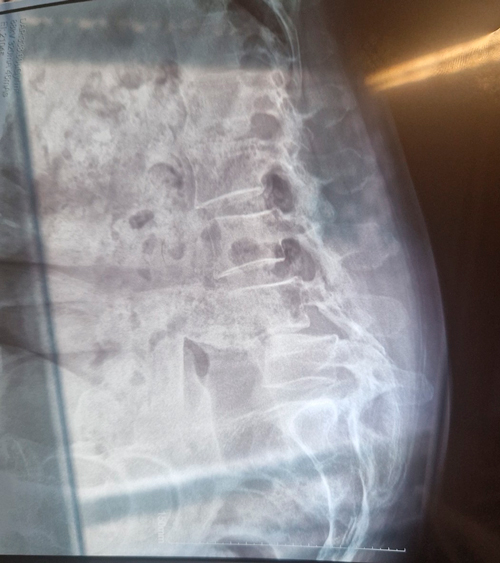

DIAGNOSI:

SPONDILOLISTESI CON STENOINSTABILITA’ L3-L5

Radiografia lombare pre-operatoria

Intervento chirurgico eseguito:

Artrodesi lombare mediante viti transpeducolari L3-L4-L5 + introduzione di cage intersomatica plif

Radiografia post-operatoria